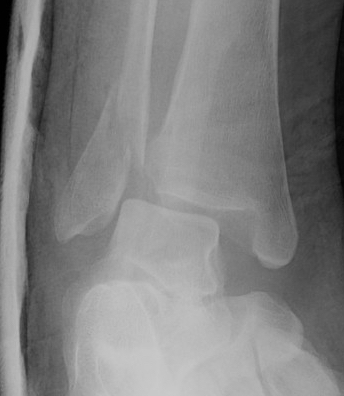

Lateral talar shift / increased medial clear space / deltoid ligament injury

Ankle Fracture Increased Medial Clear SpaceAnkle Fracture Increased Medial Clear Space 2Maisonnerve